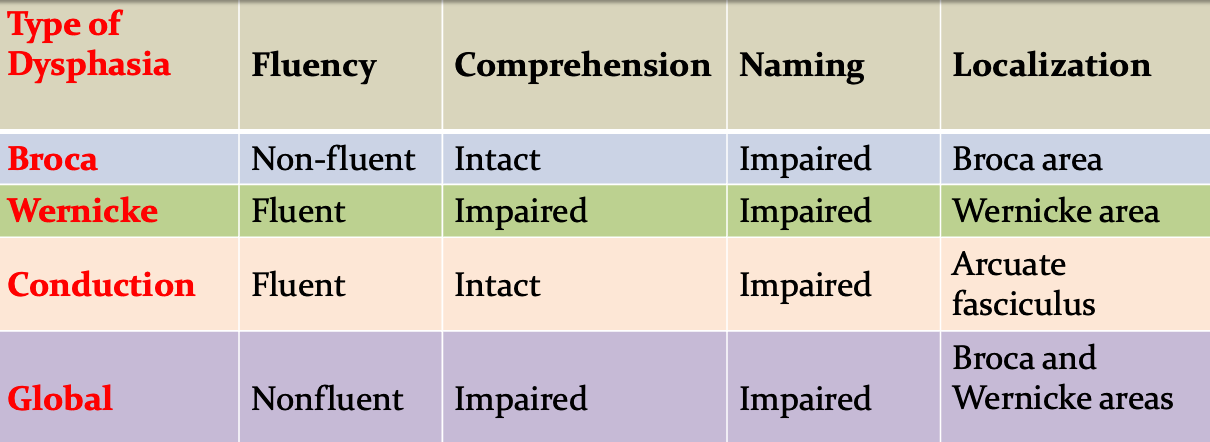

Essential Features of Common Dysphasias

Scores